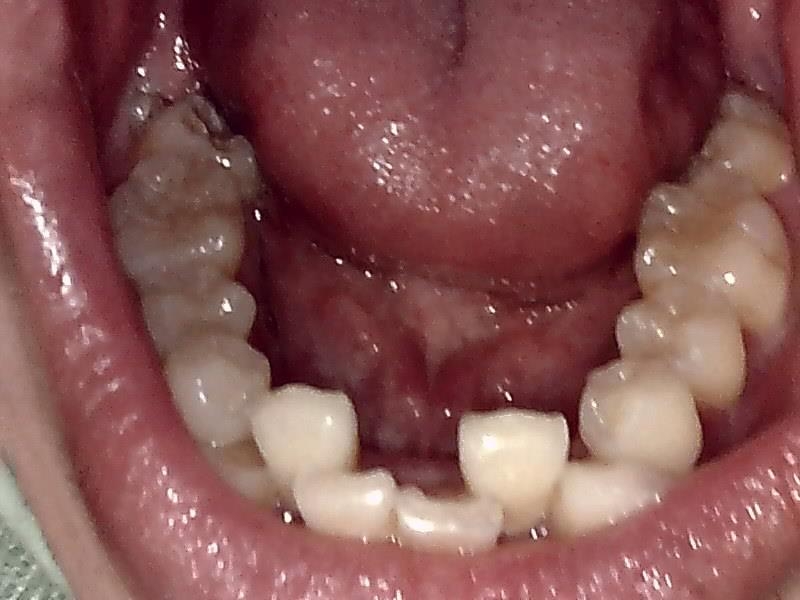

下顎咬合面観